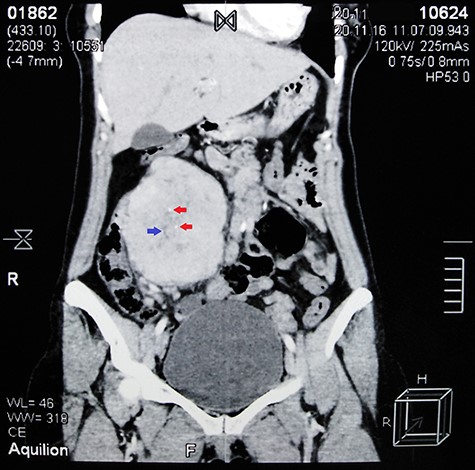

Contrast-enhanced abdominal CT scan shows a large heterogeneous mass adjacent to the inferior margin of the liver measuring (11.5 × 8.5 × 9 cm) and containing calcified areas (red arrows) and necrosis (blue arrow).

Abdominal ultrasound (US) revealed normal findings except for a 9.1 × 7.3 cm heterogeneous mass in the right hypochondrium, and an ~5 cm cystic lesion on the left ovary. Contrast abdominal computed tomography (CT) scan showed a (11.5 × 8.5 × 9 cm) well-defined mass adjacent to the inferior margin of the liver with calcified areas (Fig. 1). Para-aortic lymph nodes were not enlarged.